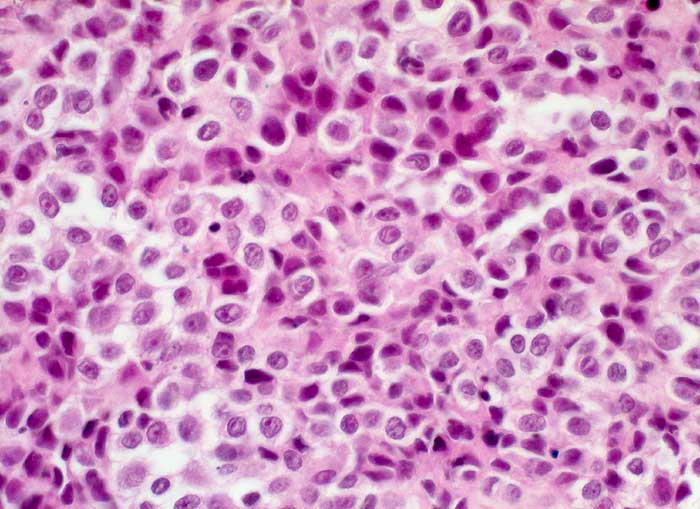

PathoPic ID 5900 - amelanotisches Malignes Melanom

amelanotisches Malignes Melanom

maligner Tumor

Pleura parietalis

Körperhöhlen, Serosa

Epitheloidzelliger solider nicht pigmentierter Tumor.

Bekanntes malignes Melanom

Zytologische Diagnose: malignes Melanom.

Histologie

400